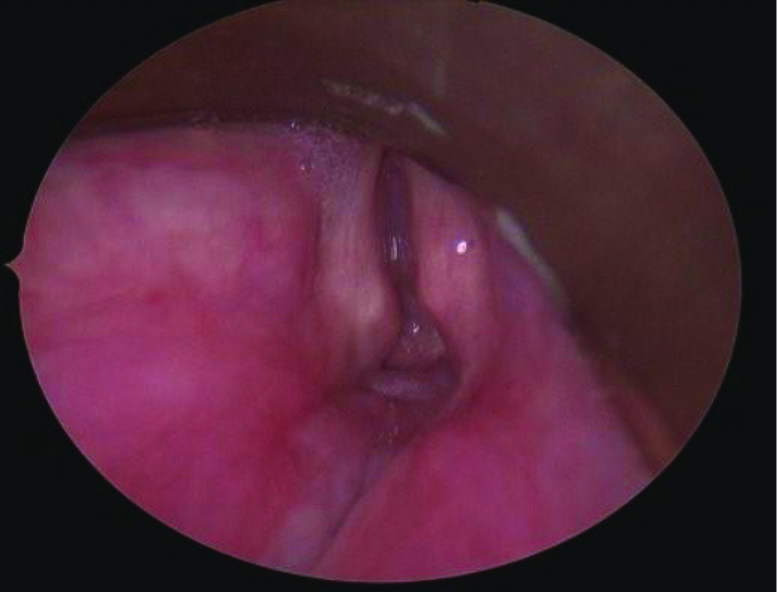

Figure 3. Operative view showing Grade 4 100% subglottic stenosis